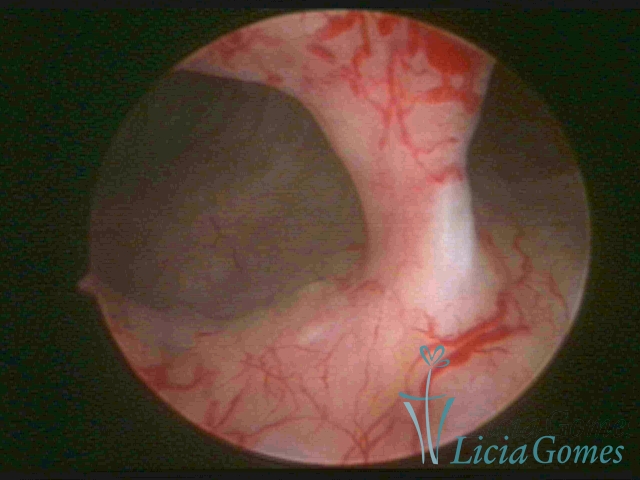

Uterus didelphys

The presence of two uterine cervices and a double vagina, similar to unicornuate uteri, with a normal covering of endometrium.